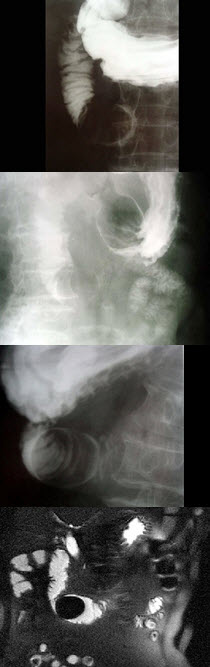

A.成骨性骨肉瘤

女,80岁,右上腹疼痛反复发作6月,加重2天,曾有胆囊炎及胆结石病史,影像检查如图,最可能的诊断为()

A.十二指肠息肉

B.十二指肠巨大胆结石(胆囊十二指肠瘘)

C.十二指肠蛔虫

D.十二指肠间质瘤

E.十二指肠腺瘤